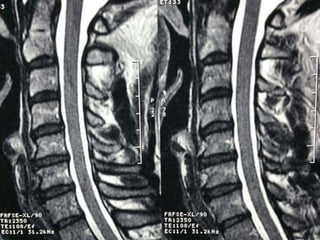

77 year old woman with h/o hand weakness/numbness/ataxia

Prior acdf 14 years ago

77 year oldwoman with h/o hand weakness/numbness/ataxia Prior acdf 14 years ago